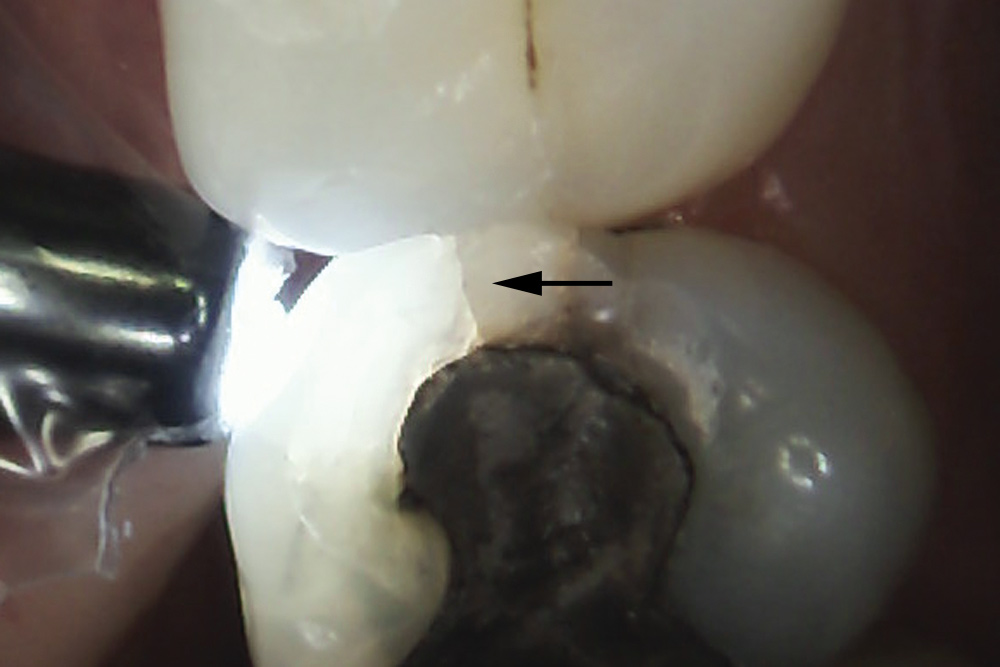

The use of fiber-optic transillumination for crack diagnosis is well documented in the literature.1-3,5,6,8-10,12,15-17,21-23 Teeth with significant cracks transilluminated with a fiber-optic light source will show a well-defined demarcation of blocked illumination at the crack lines, whereas structurally sound teeth will dissipate the light gradually throughout the tooth structure (Figure 3).22 While a variety of transillumination devices have been used to reveal cracks, pen-sized cordless units with a highly collimated light source and that are specifically manufactured for this purpose are ideal for this diagnostic technique. This is mainly because they emit the proper amount of light intensity to highlight cracks, and viewing can be done directly with the eye without using a protective device.22

Fig 3. Transillumination of an asymptomatic maxillary left second premolar blocked by an enamel marginal ridge crack (arrow) (mesio-occlusal view).

Figure 3